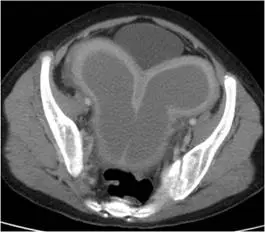

13 歲女性病患,月經未來且下腹痛,故接受電腦斷層檢查,結果如下圖。其最有可能的診斷為何? 圖片

本題考查「子宮融合異常合併處女膜未穿孔(uterine fusion abnormality with imperforate hymen)」的電腦斷層(CT)影像特徵與臨床表現。13 歲青春期女性出現原發性月經未來(primary amenorrhea)合併週期性下腹痛,此組合高度提示先天性婦科解剖異常導致月經血液滯留。

本題 CT 橫切面影像顯示骨盆腔內有一個巨大的雙葉狀(bilobed)低密度囊性結構,呈「左右對稱分葉」或「W 形」外觀,幾乎佔據整個骨盆腔。具體所見:

• 雙側分葉囊腔:兩個分別位於左右兩側的囊性腔室,中間有薄隔膜或輕微凹痕分隔,形成雙葉結構(figure-of-8 / bilobed appearance)。此形態高度符合子宮雙子宮(uterus didelphys)或子宮融合異常,雙側各有積血腔室(hematometra)

• 腔室壁平滑:囊腔壁薄而均勻,無明顯壁結節或鈣化,不符合惡性病灶

• 低密度內容物:內容物接近水密度,符合積血(hematocolpos/hematometra)或積液(hydrocolpos)的影像表現

• 膀胱受壓:前方膀胱受到大型盆腔腫塊向前推擠,可見膀胱被壓扁

• 整體占位效應:病灶充滿整個小骨盆,對稱且邊緣整齊